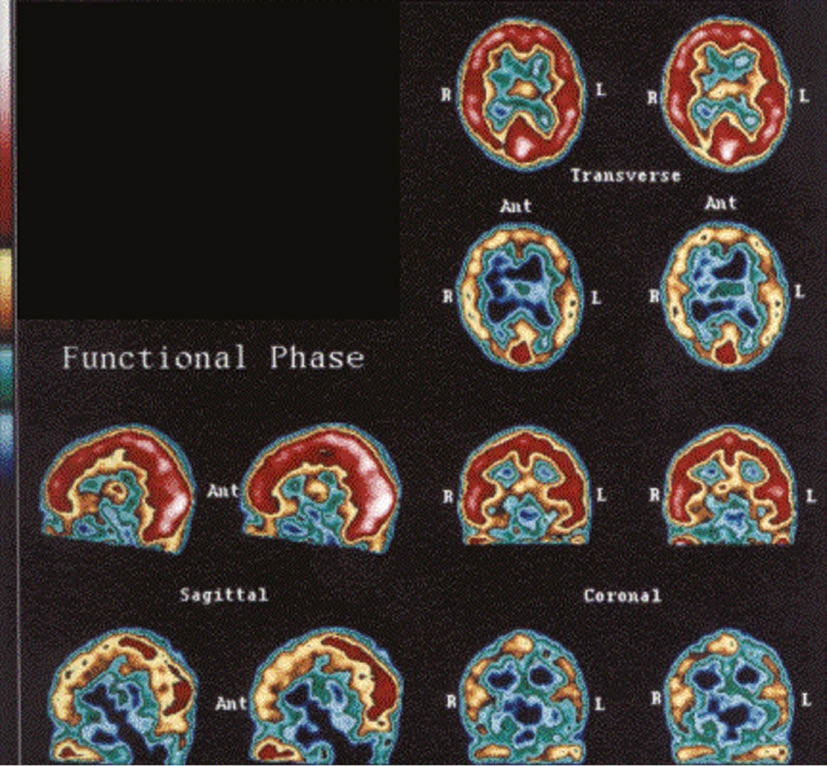

Brain SPECT scan

Normal SPECT brain scan – smooth, uniform, distinct outlines, no rough edges or holes in cerebral hemispheres or abnormal temporal lobes. Abnormal SPECT brain scan – rough edges, holes in cerebrum, temporal lobes obliterated or poorly outlined.